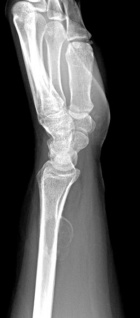

32 y/o spanish speaking female with one month of intermittent pain associated with a mass in left wrist. Pain began after playing the drums. No constitutional sx.

PE: Palpable 2cm mass dorsal distal forearm, TTP w/o crep, no LAN, erythema, edema, neurovascularly intact